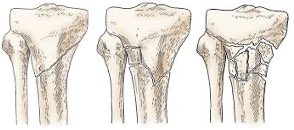

🔹 كسر الظنبوب (Tibia):

- كسر ثابت (Fixed fracture): عندما تبقى قطع العظم في وضعها الصحيح.

- كسر قلعي (Avulsion fracture): عندما تخرج العظام عن وضعيتها.

- كسر مفتوح (Open fracture): عندما يخترق العظم الجلد.

- كسر الهضبة الظنبوبية (Tibial plateau fracture).

- كسر الظنبوب عند مفصل الركبة (Proximal tibial fracture)

- كسر المحور (Tibial shaft fracture): يكون في منتصف العظمة

- كسر عند مفصل الكاحل (Distal tibial fracture)

- كسر الغصن النضير (Greenstick fracture) لدى الأطفال

- كسر الإجهاد (Stress fracture): بسبب الضغط الكبير على العظم